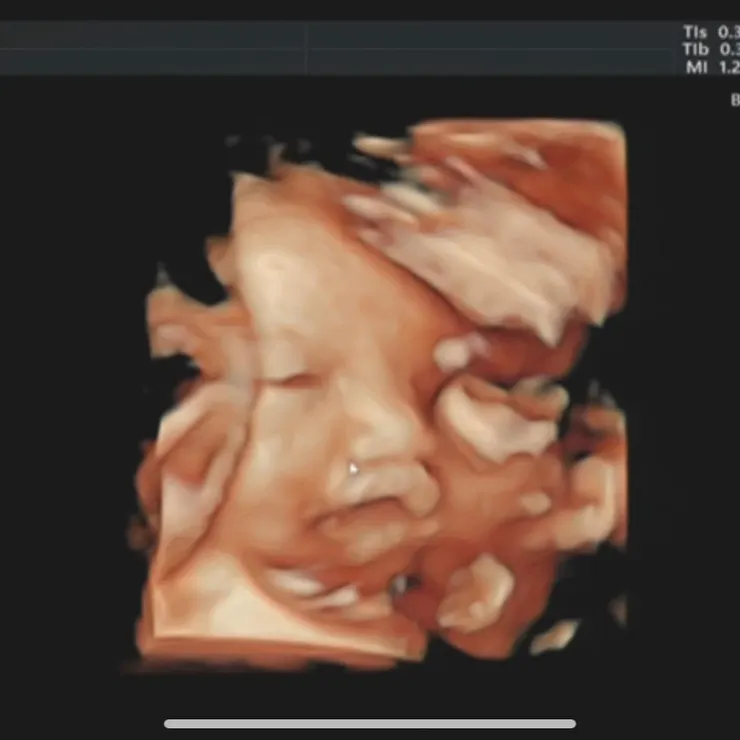

- 第一次看到4D超音波

看到寶貝半睜開眼、小鼻子、小嘴巴的4D照,覺得很新奇👀

覺得鼻子很像我XD(純粹是媽咪本人的想像),拜託拜託~連皮膚眼睛都像我就更好了~

4D超音波好療癒啊~~